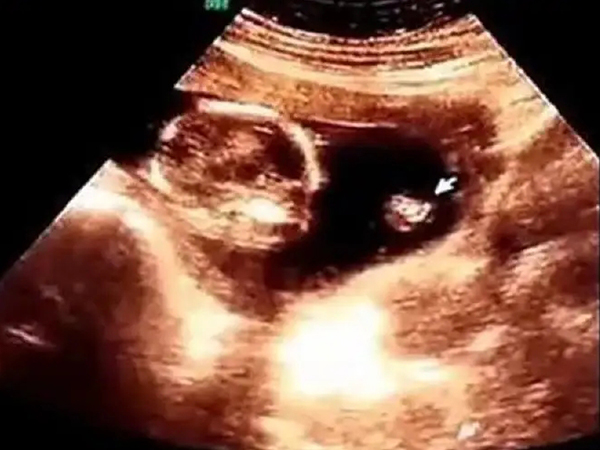

B超检查孕期一定要做